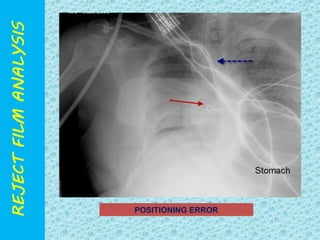

POSITIONING ERROR